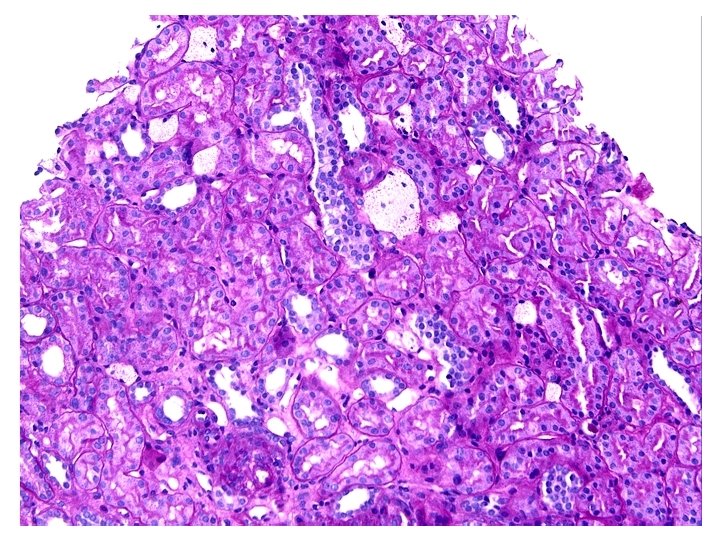

Patient 11 m with nephrotic range proteinuria History

Patient 11 m with nephrotic range proteinuria

History • 11 M with nephrotic range proteinuria – U P/C 7 • Microscopic hematuria

Diagnosis • Findings c/w Alport’s Syndrome, Autosomal Recessive Type • Mild Interstitial Fibrosis

Alport’s Syndrome • Recurrent hematuria • Nerve deafness • Usually presents in early 20’s • Classic renal biopsy features by EM – Thickened and Thinned GBM – Lamination and Rarefaction – Grains